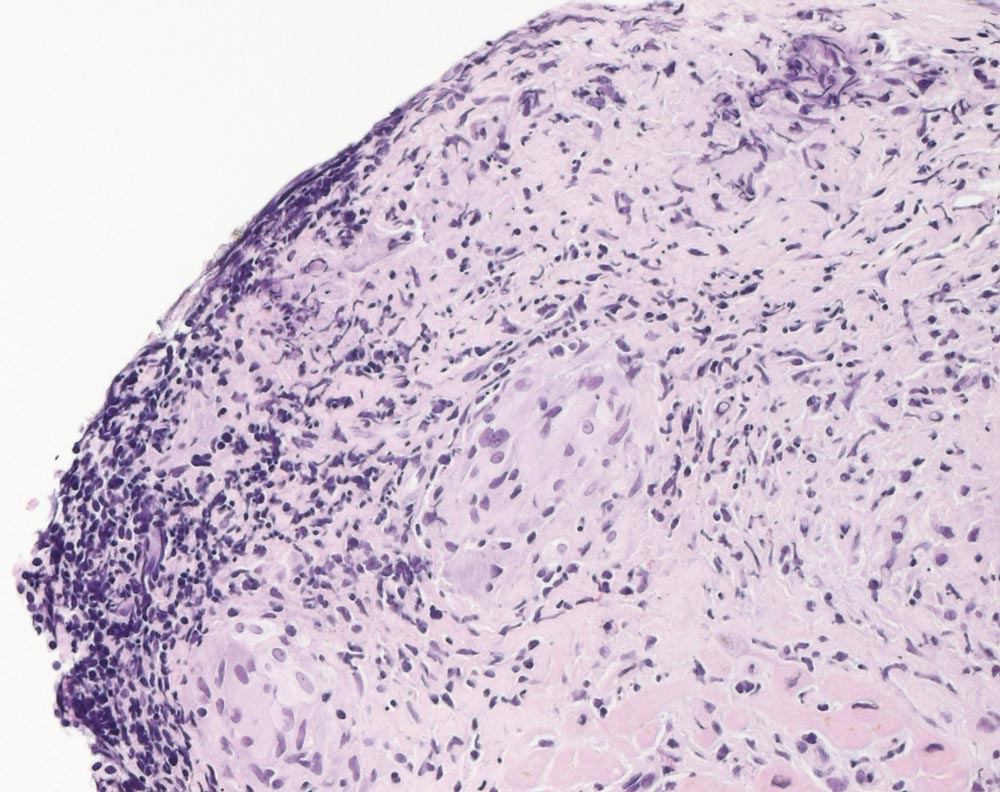

PathoPic ID 10020 - Sarkoidose des Myokards

Sarkoidose des Myokards

Systemerkrankung/Immunpathologie

Herz rechts

Kardiovaskuläres System

Endokardiale fibrosierte epitheloidzellige Granulome.

AV-Block. Late enhancement in der MRI Untersuchung septal. Keine extrakardiale Sarkoidosemanifestationen. DD Sarkoidose, Myokarditis, andere chronisch entzündliche Erkrankung des Myokards.

Histologie

200